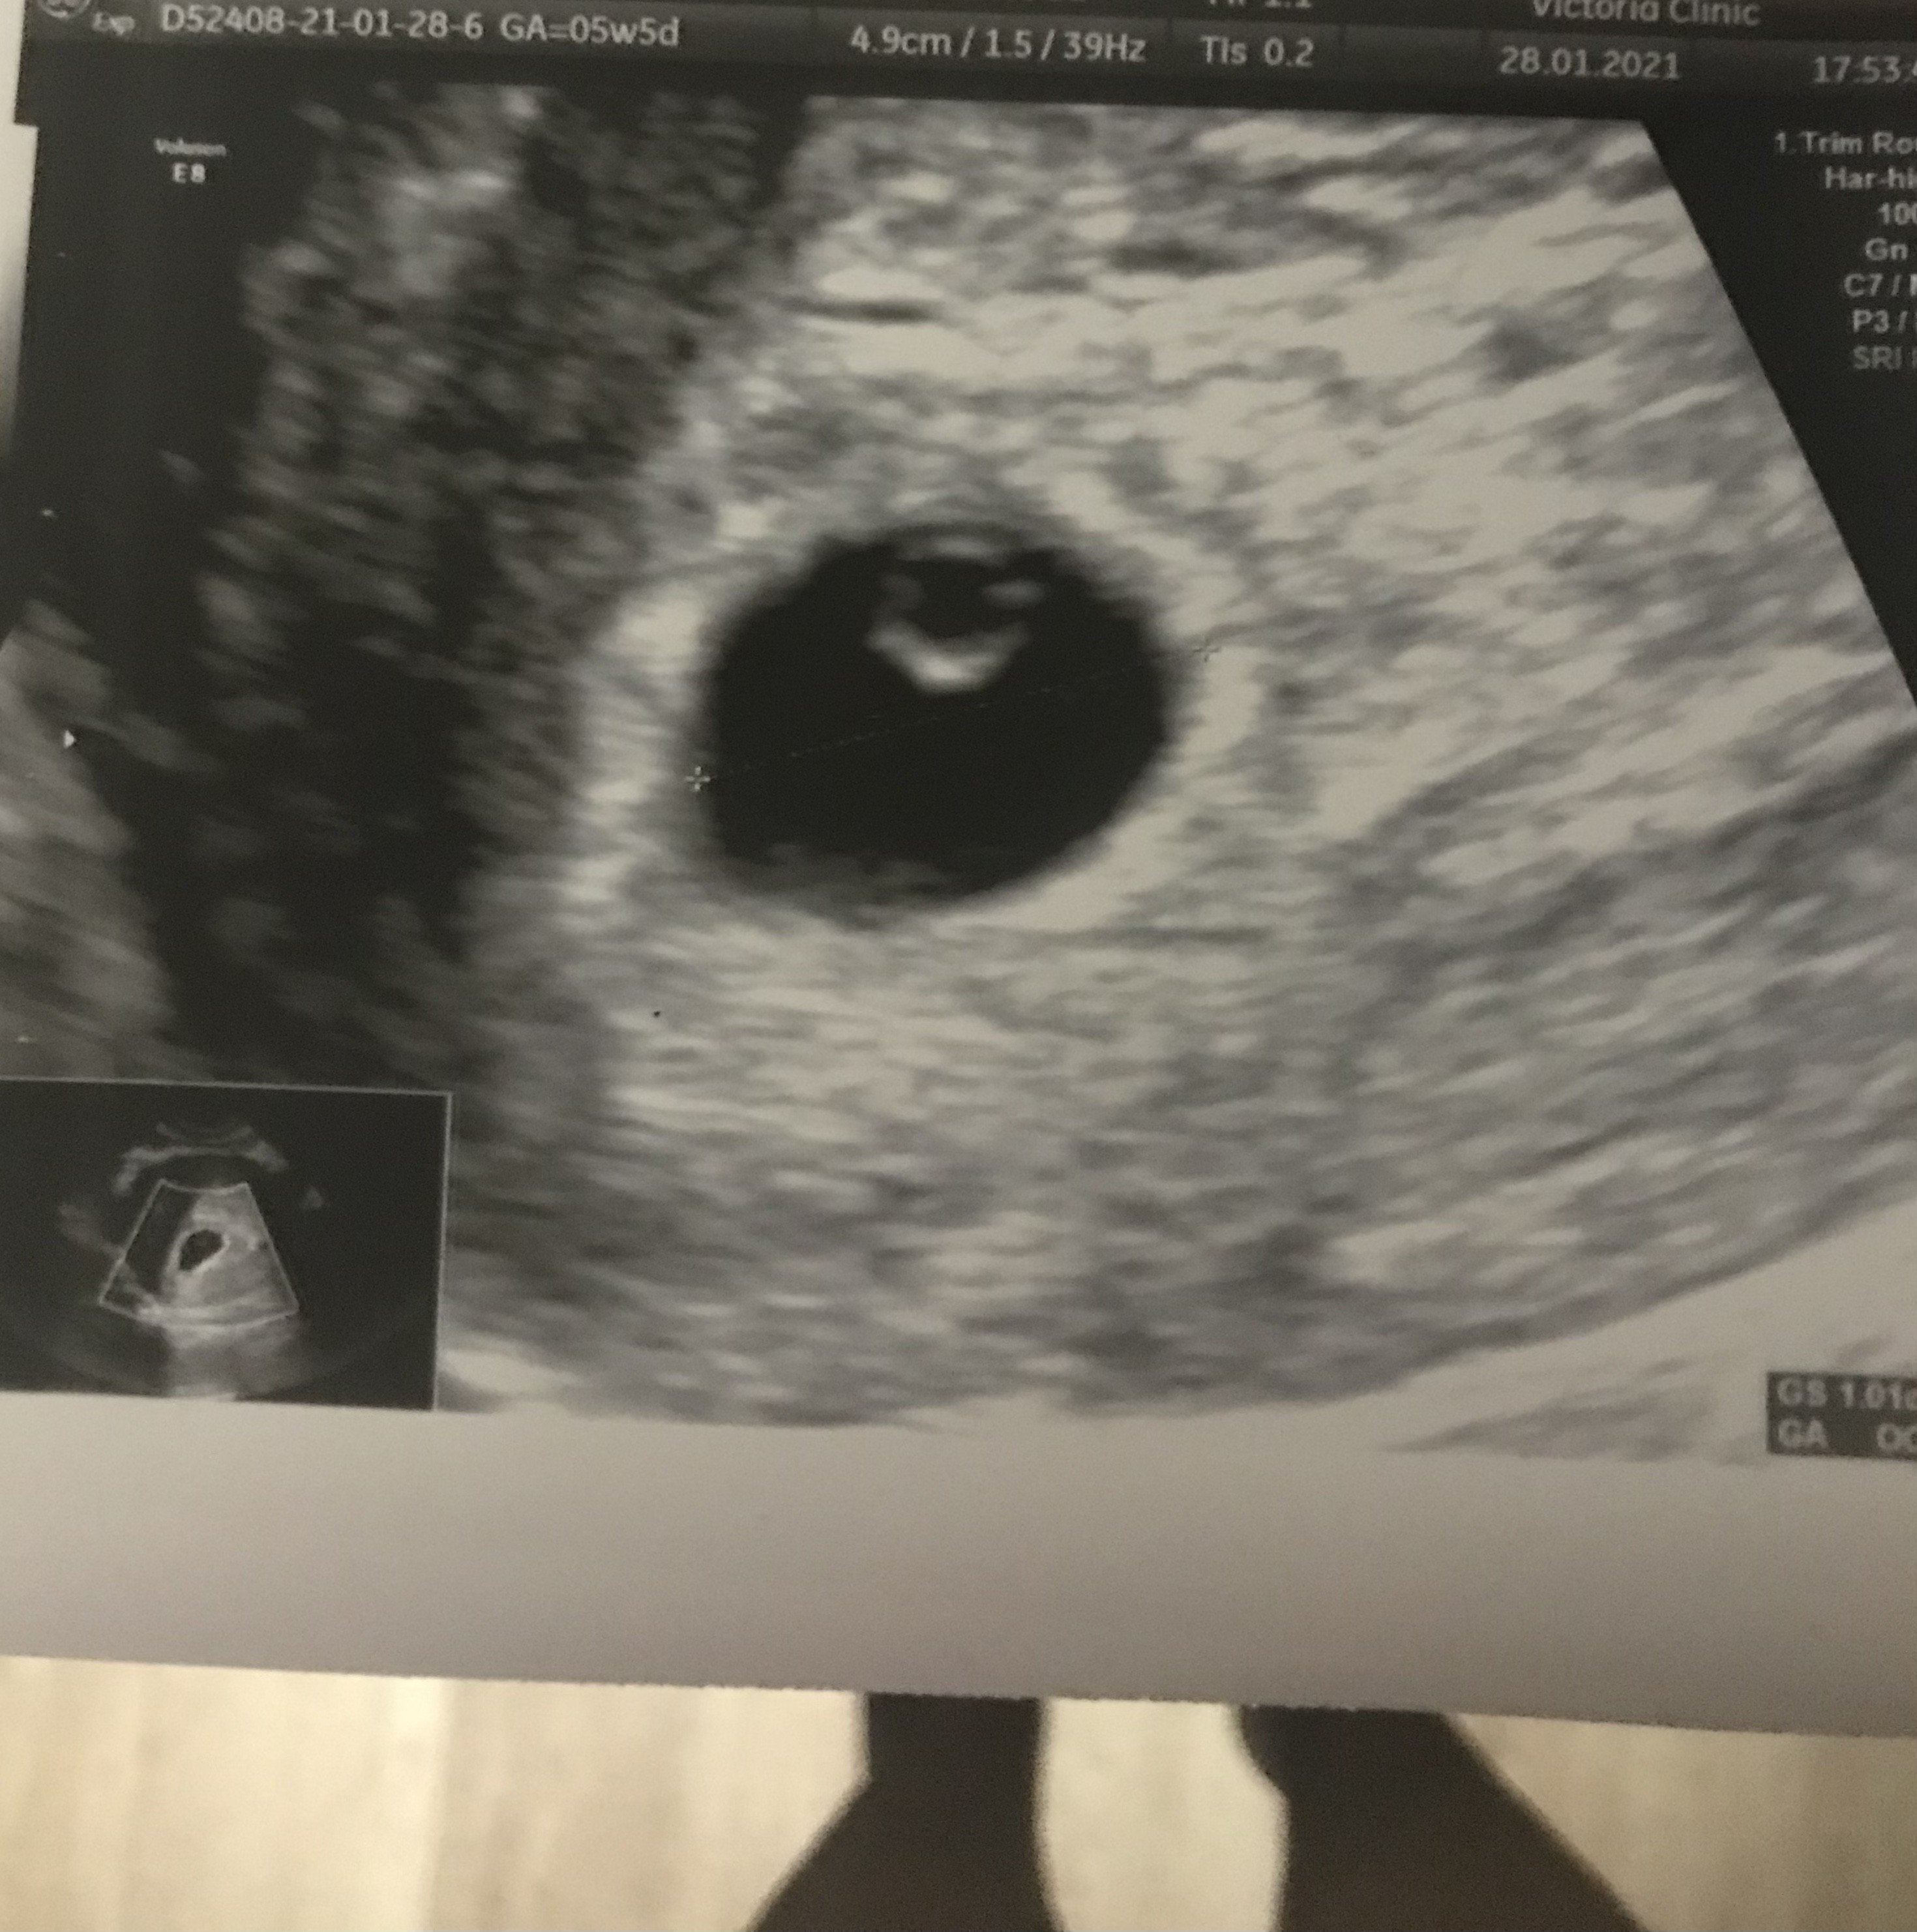

Kochana ja w 5+5 widoczny tylko pęcherzyk ciążowy i pęcherzyk żółtkowy teraz czeka mnie wizyta 2 lutego i zobaczymy czy coś więcej widać . 💁‍♀️ I ja z kolei biorę luteinę bo w dzień wizyty miałam brązowe plamienia 🙈

No wlasnie, z racji ze bylam pierwszy raz tak wczesnie na usg (5+5) to powiedzcie mi co oznacza taka jakby bańka w pecherzyku? Dokladnie widzialam pecherzyk i w srodku taka bańka okrągła... u was to jakos inaczej wyglada...

Tak to mniej wiecej wygladalo, ale sam ten okragly babelek...nigdy nie uswiadczylam takiego widoku, zastanawiam sie czy jest ok...Zobacz załącznik 1233036

Bardzo ładny pęcherzyk żółtkowy. To dobry znak, bo najprawdopodobniej po 1-2 dniach pojawi się zarodek. Wygląda na to, że narazie wszytko rozwija się książkowo jak na ten etap ciąży. Myślę, że na najbliższej wizycie zobaczysz serduszko ✊✊✊